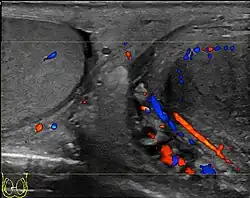

- Ultrasound scanning

- Lefort C, Thoumas D, Badachi Y, et al. (July 2001). "Orchites ischémiques: À propos de 5 cas diagnostiqués en écho-Doppler couleur" [Ischemic orchiditis: review of 5 cases diagnosed by color Doppler ultrasonography]. Journal de Radiologie (in French). 82 (7): 839–42. PMID 11507447. INIST 1080037.

- Chung JJ, Kim MJ, Lee T, Yoo HS, Lee JT (September 1997). "Sonographic findings in tuberculous epididymitis and epididymo-orchitis". Journal of Clinical Ultrasound. 25 (7): 390–4. doi:10.1002/(SICI)1097-0096(199709)25:7<390::AID-JCU7>3.0.CO;2-5. PMID 9282805. S2CID 23653479.